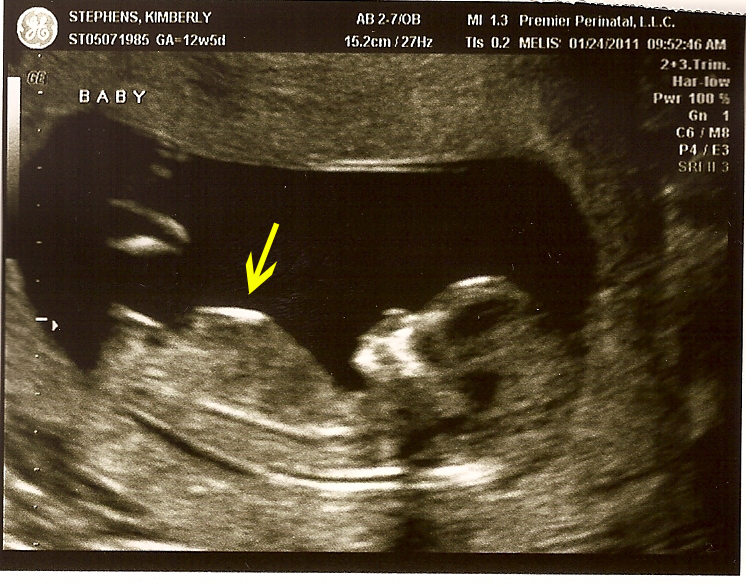

Normally a baby’s organs develop faster than their the body has room for, so God made it so the organs develop outside the body at first, then go through the umbilical cord into the belly at about week 10. By the time 11 weeks roll around, they should already be through, and the hernia they pass through should already have healed. When the doctor looked at our baby, he saw what looked like organs still developing on the outside of its belly (see the arrow in the picture, it’s the cloudy part next to the tube-y looking thing). The term for this issue is Gastroschisis. It’s a birth defect in which an infant’s intestines stick out of the body through a defect on one side of the umbilical chord. It’s not a life-threatening defect. It is usually taken care of by giving birth through C-section and immediate surgery. We would have to wait a few months to take our baby home.

Yesterday morning we met with the specialist. We got to see our baby again on the ultrasound. You’ll notice the distinct lack of organs sticking out of its belly at the arrow. The doctor did too. His comment was, “I don’t know what they saw on the first ultrasound, but your baby looks perfectly fine to me. When people don’t look at these ultrasounds all day, every day like we do, they tend to misread them I guess.”